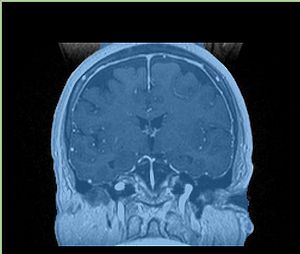

A distinctive feature of BRAINSFit tool is the ability to automatically detect head region of interest, which is used for collecting intensity samples during metric calculation. Below is the overlay of such ROI in light blue overlayed with the image for Case10. This functionality appears to work consistently for all the cases used in the comparison.

• Case10